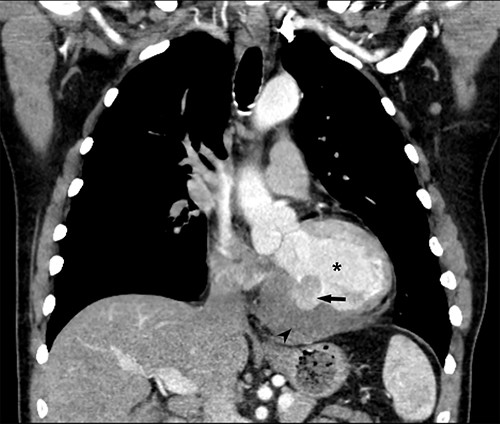

He returned 5 weeks later complaining of 72 hours of malaise, fevers and chest pressure. He was tachycardic and hypotensive but intermittently responsive to fluid resuscitation. He noted reluctance to present for evaluation, given concerns regarding COVID-19 exposure if he was hospitalized. A computed tomography (CT) of the chest noted a left ventricular irregularity and adjacent thrombus (Fig. 1). Echocardiography revealed an ejection fraction of 35%, a large pericardial effusion and an aneurysmal-appearing inferolateral left ventricular wall with intrapericardial thrombus (Fig. 2).

Coronal CT demonstrating left ventricular wall defect and intrapericardial thrombus; asterisk = left ventricular cavity, arrow = left ventricle free wall defect, arrowhead = thrombus.